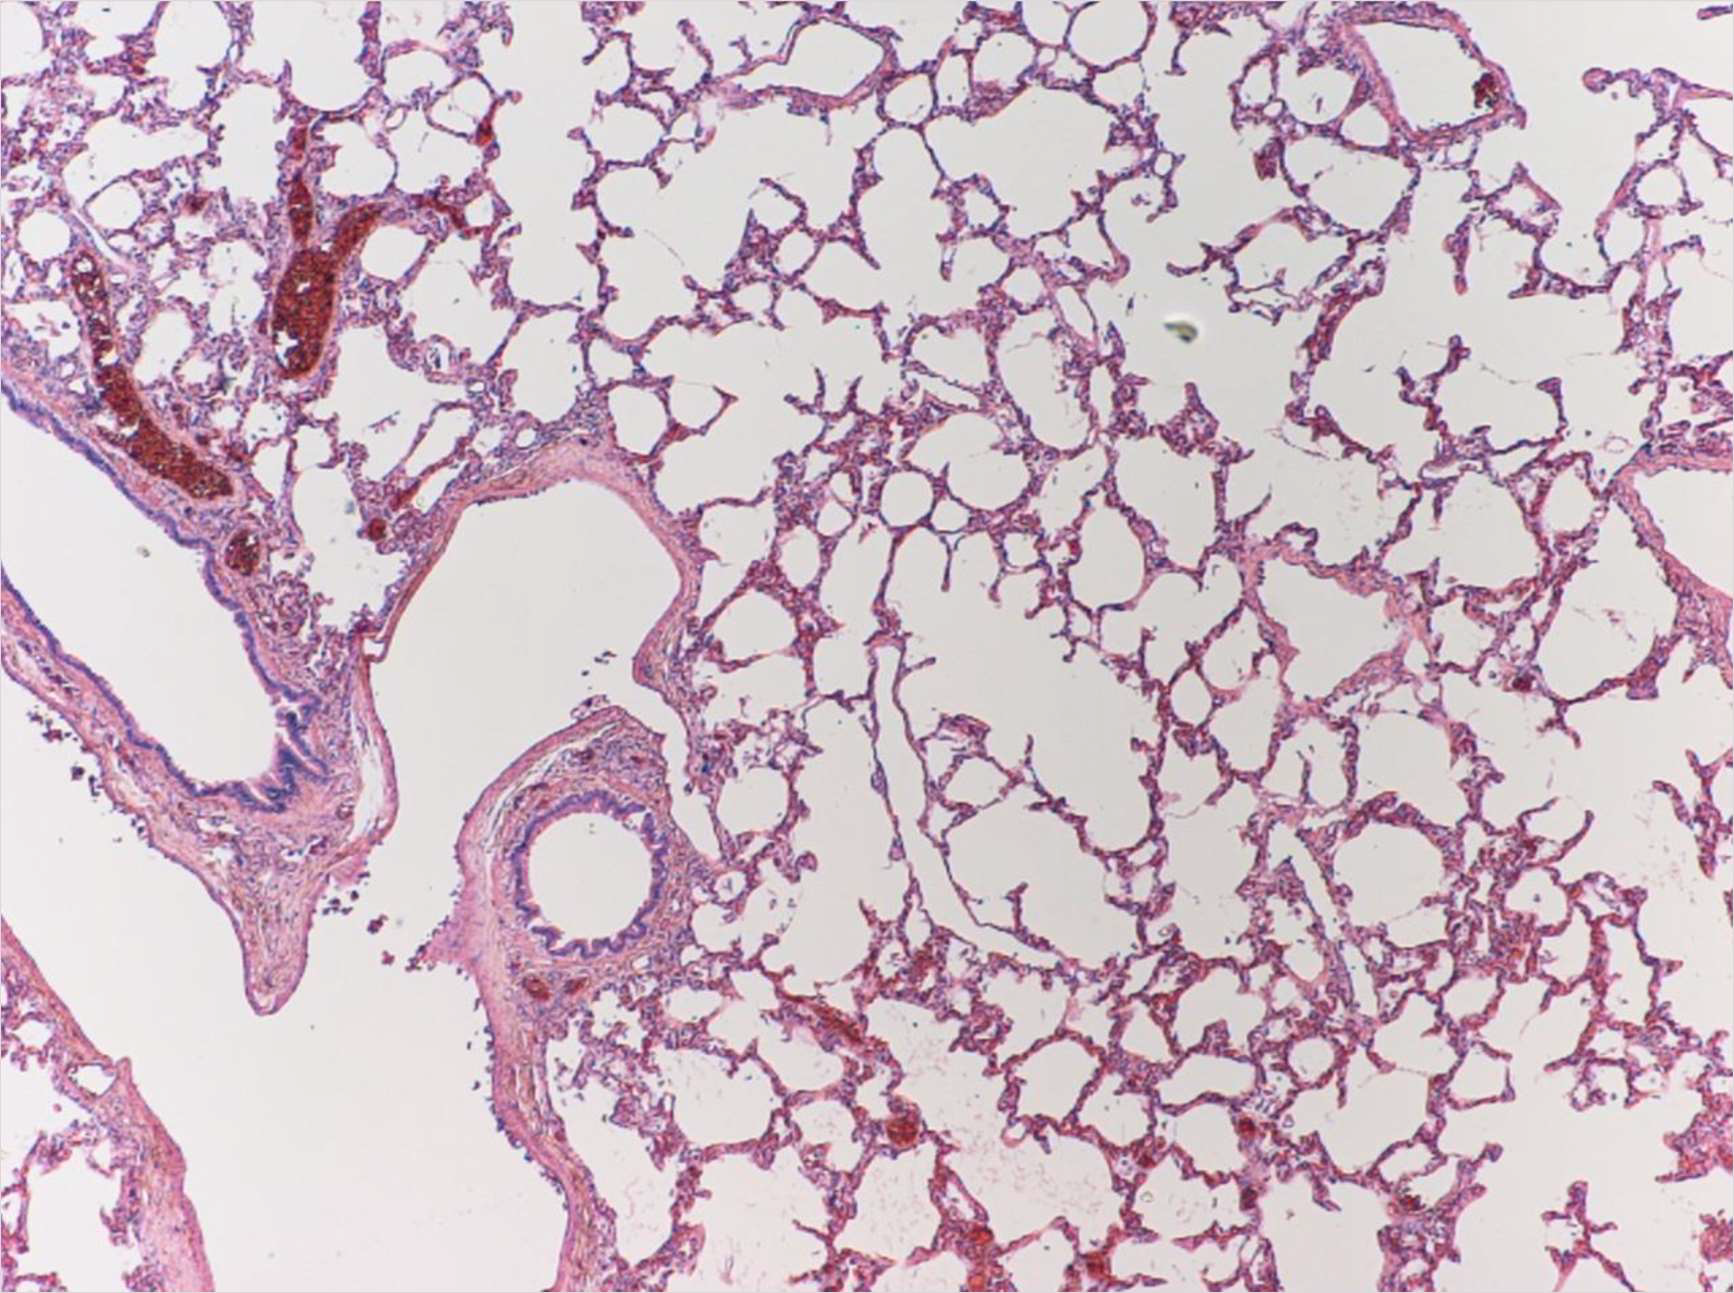

6. MedullaLung

71. Bronchiole,

2. Vein,

3. Alveolar wall,

4. Capillary,

6. Smooth muscle,

7. Blood vessel,

8. AlveoliKidney